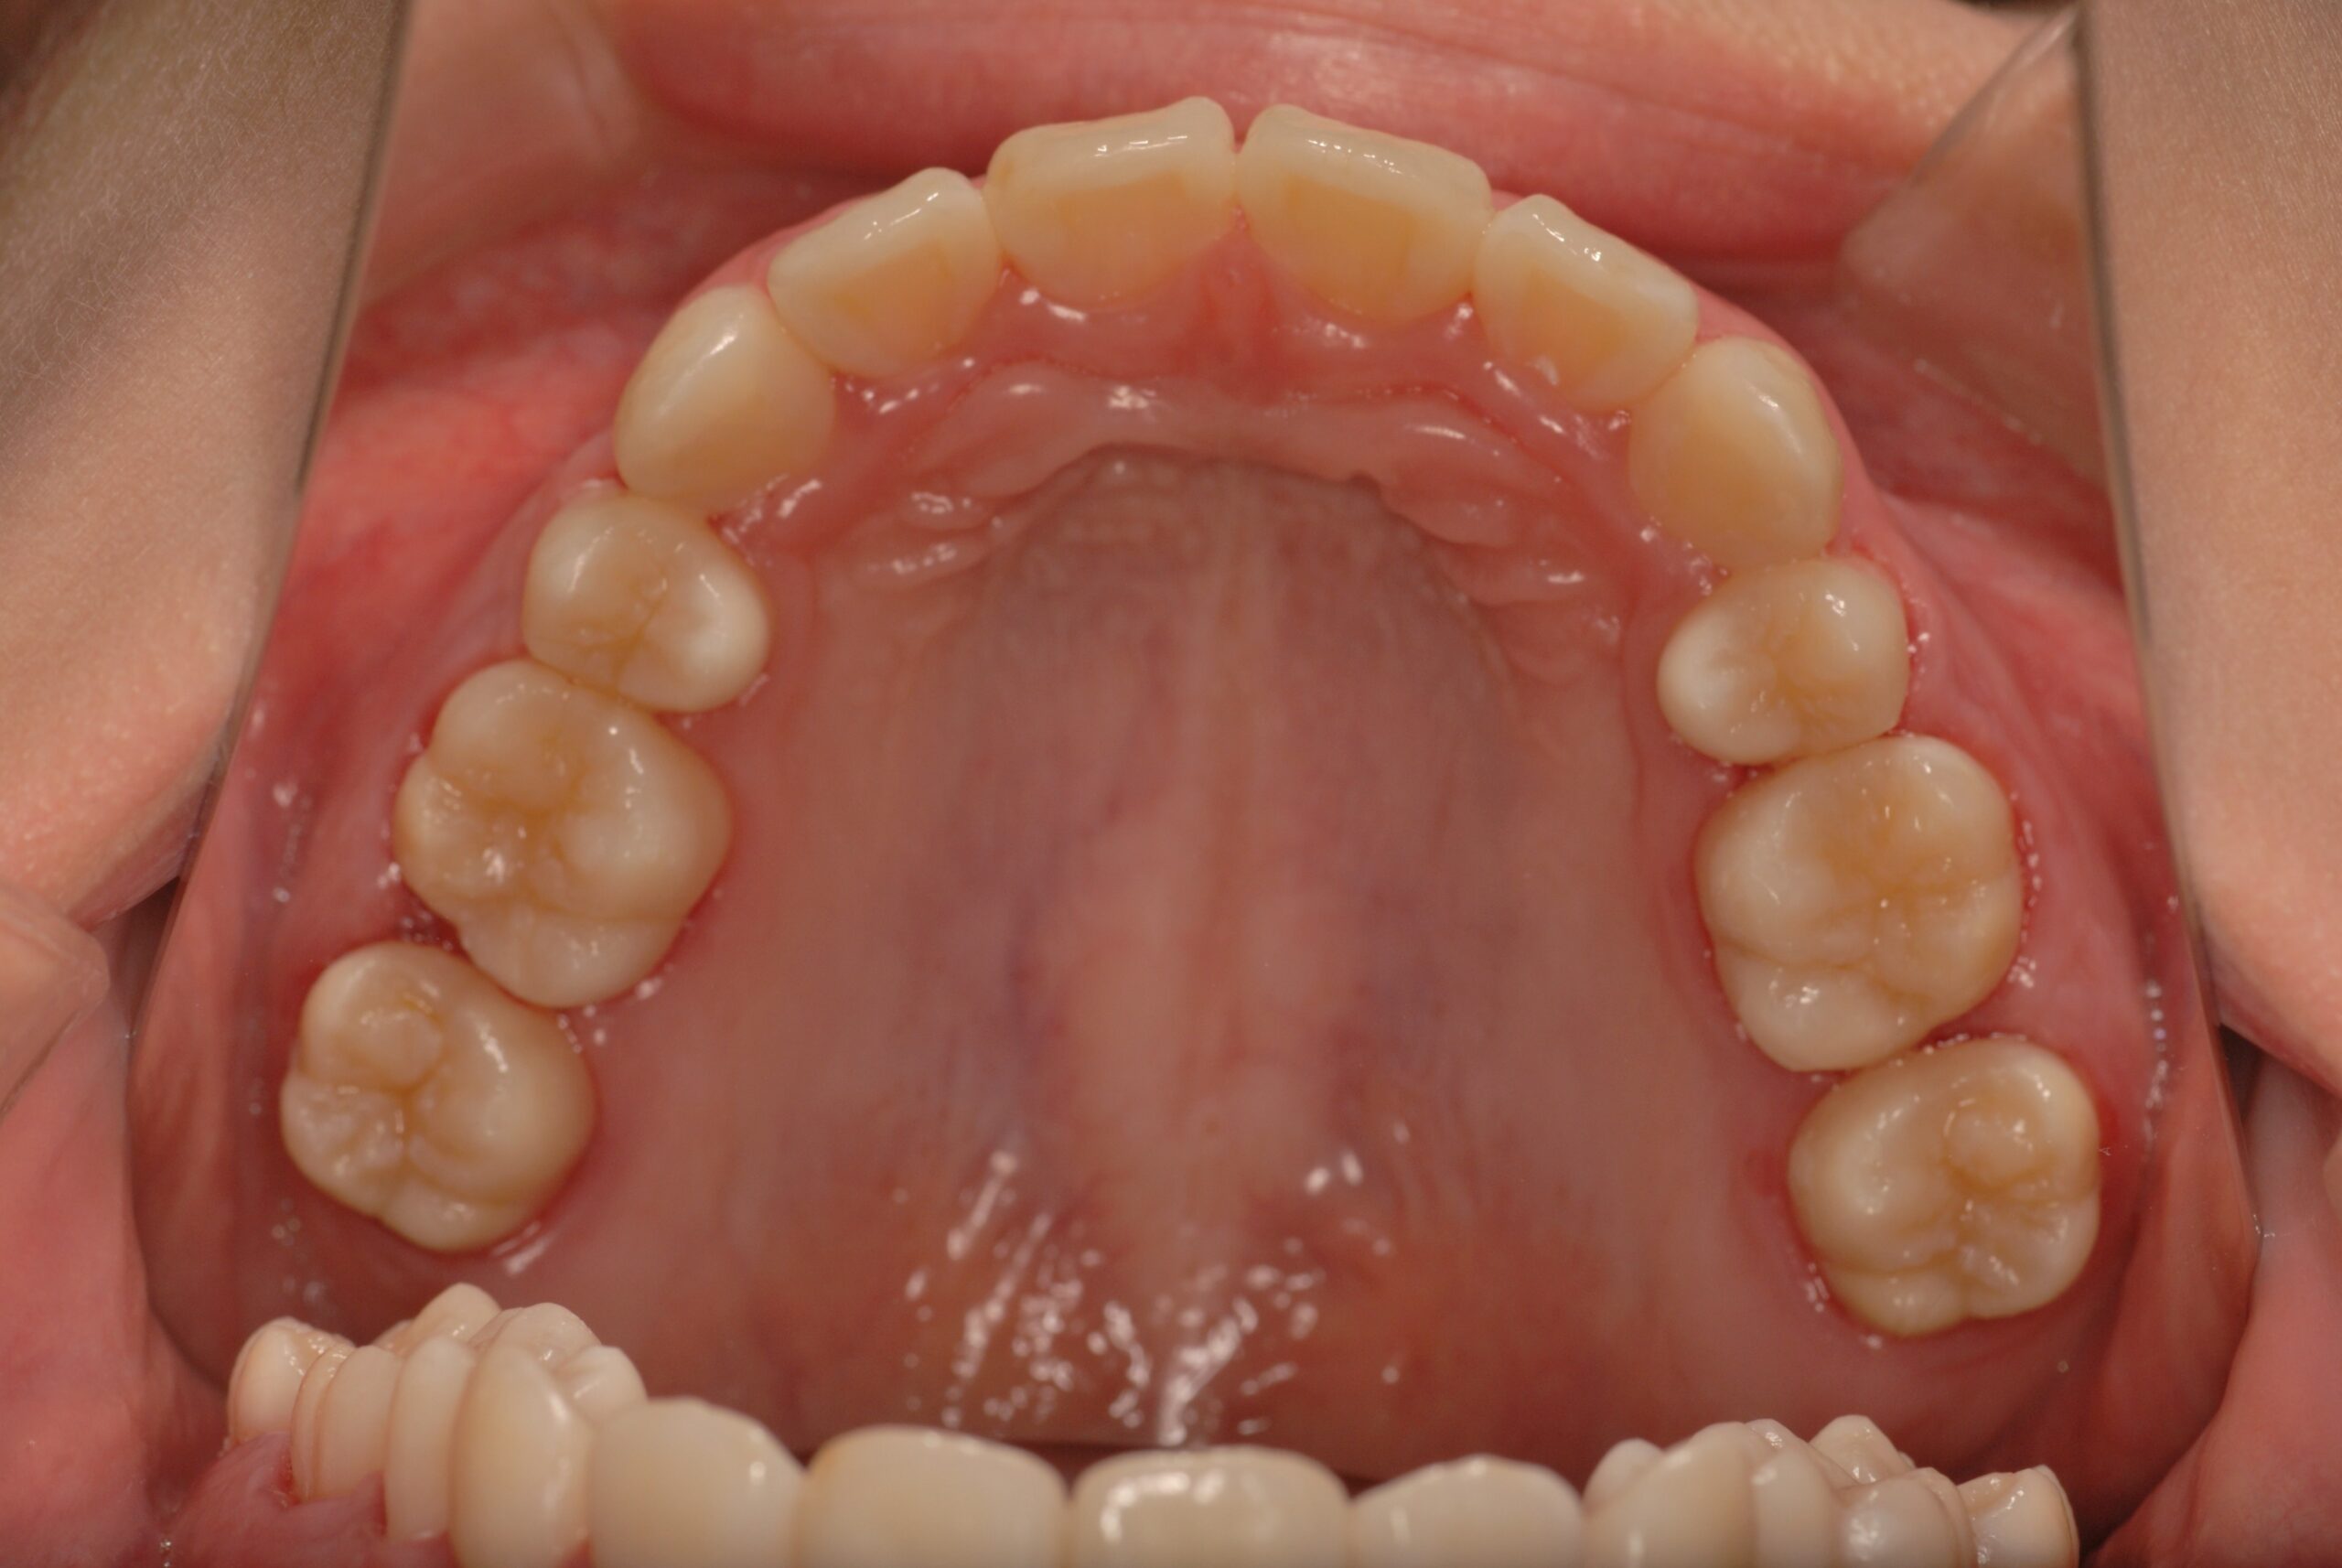

Before

- 診断名、治療内容

- 上顎前突、叢生。 上下顎第一小臼歯を抜歯し、抜歯空隙を利用し、顎外固定装置としてヘッドギヤを併用しながら、上顎前歯を可及的に後退させる。